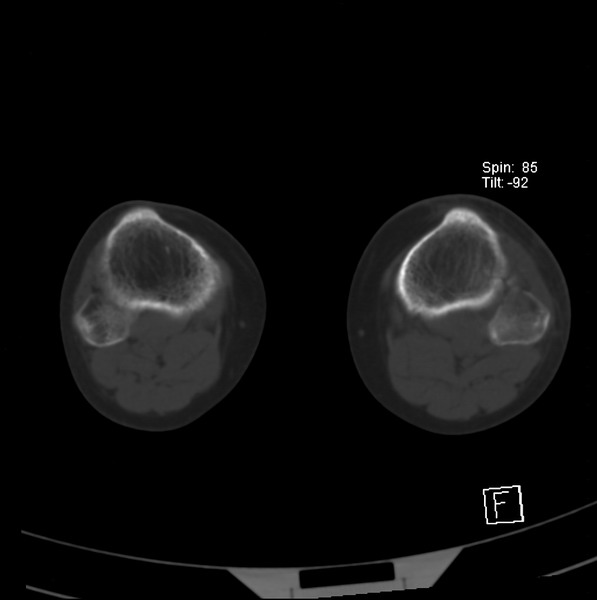

标题: CT21917:右腓骨小头是否骨软骨瘤? [打印本页]

标题: CT21917:右腓骨小头是否骨软骨瘤?

女、43.

不是骨软骨瘤,“牵拽征”,正常变异。有平片吗?

正常变异,“牵拽征”,比目鱼肌牵拽.